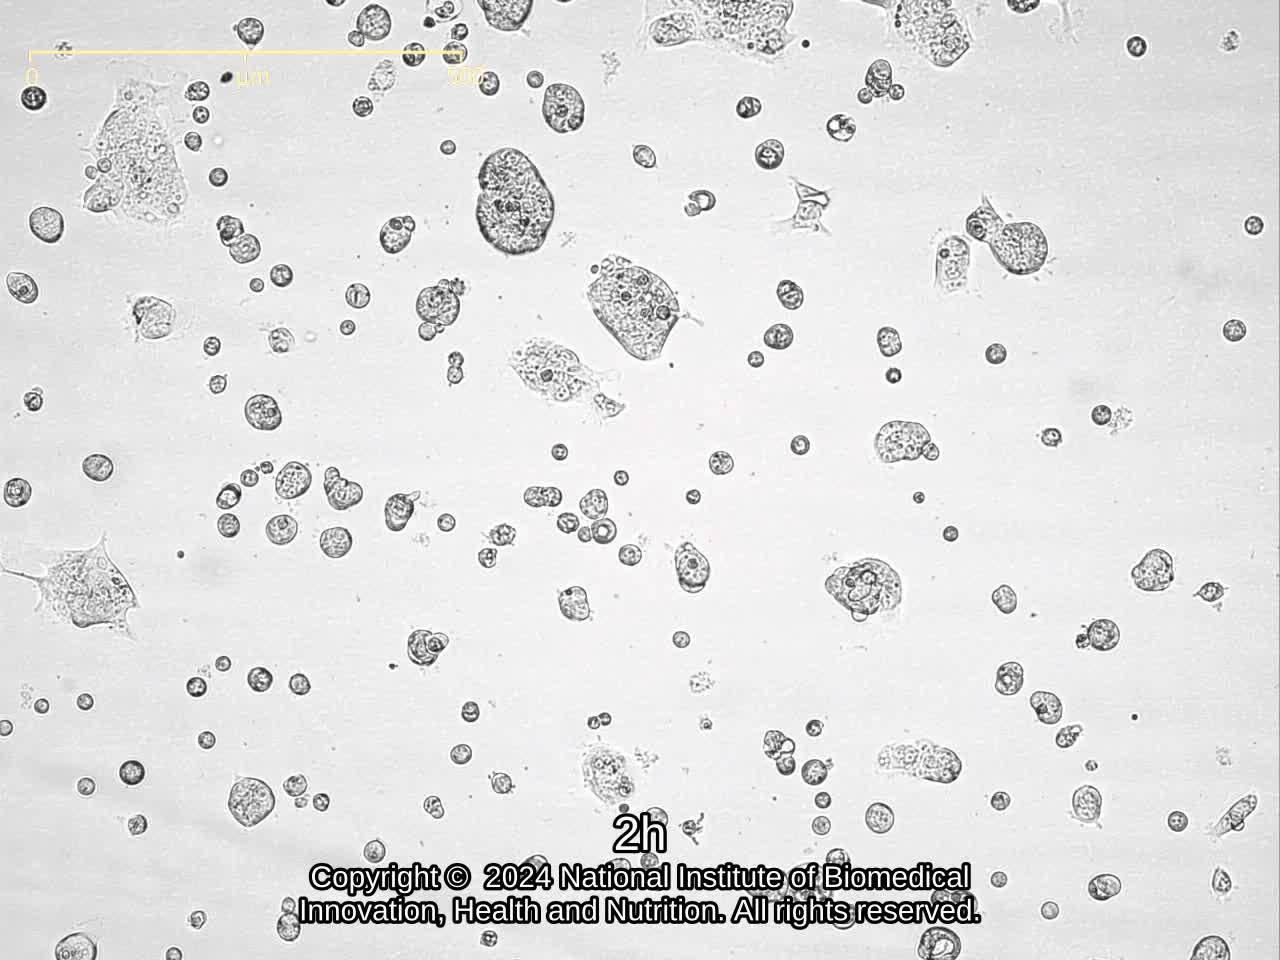

| Images |

![]() ![]() ![]() ![]() ![]() ![]() ![]() ![]() ![]() |

|